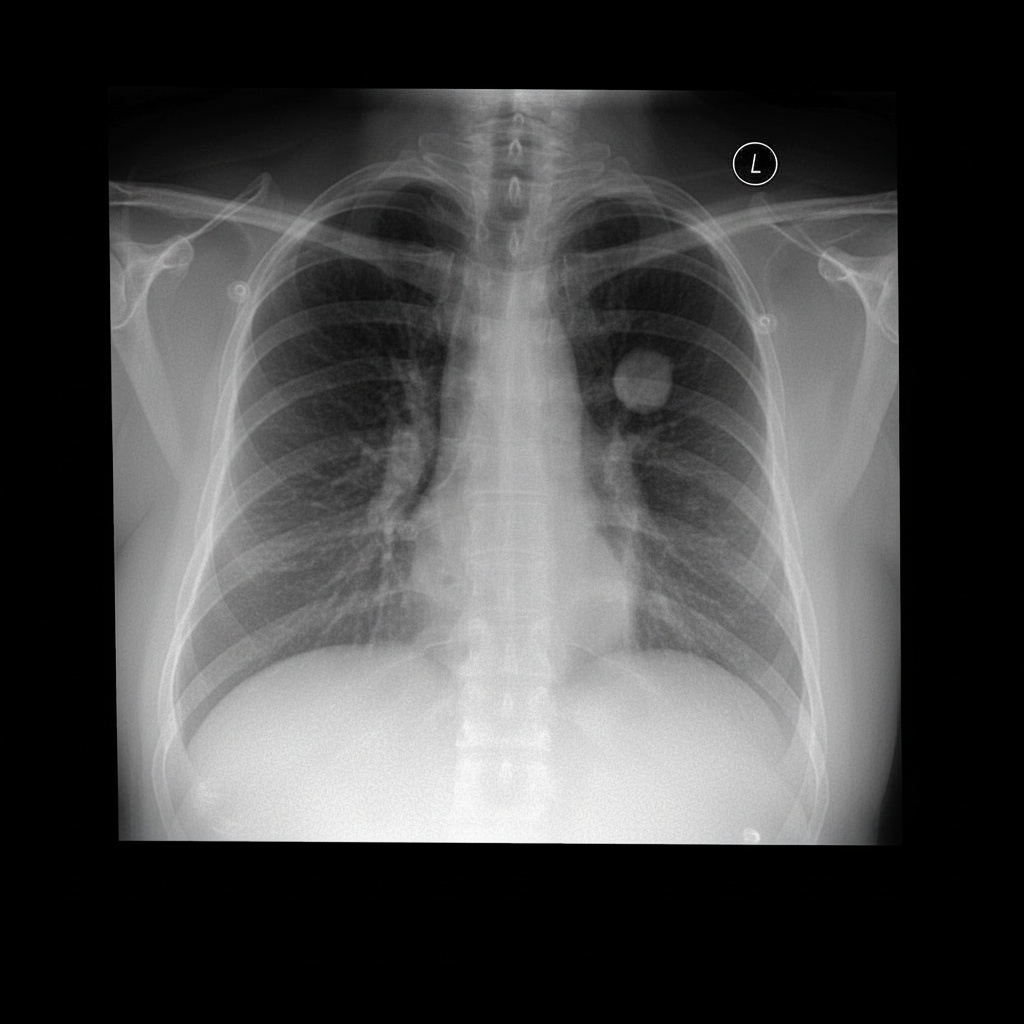

Med-Banana-50K is a large-scale medical image editing dataset released by the National University of Singapore in 2025. The related research paper is as follows: Med-Banana-50K: A Cross-modality Large-Scale Dataset for Text-guided Medical Image EditingIt aims to cover bidirectional editing tasks of lesions under various medical imaging modalities and disease conditions. This dataset contains over 50,000 medical image editing samples, along with approximately 37,000 failed editing attempts and their complete evaluation logs. Based on real clinical medical images, the dataset covers three medical imaging modalities: chest X-ray, brain MRI, and fundus imaging, encompassing 23 disease types. Each sample supports both lesion addition and removal editing, with the editing process generated using the Gemini-2.5-Flash-Image model. All samples underwent an automated evaluation process based on LLM-as-Judge, assessing aspects such as instruction compliance, structural rationality, image realism, and fidelity of original information. Up to five rounds of iterative optimization were performed as needed, and all evaluation results and processes were fully recorded.